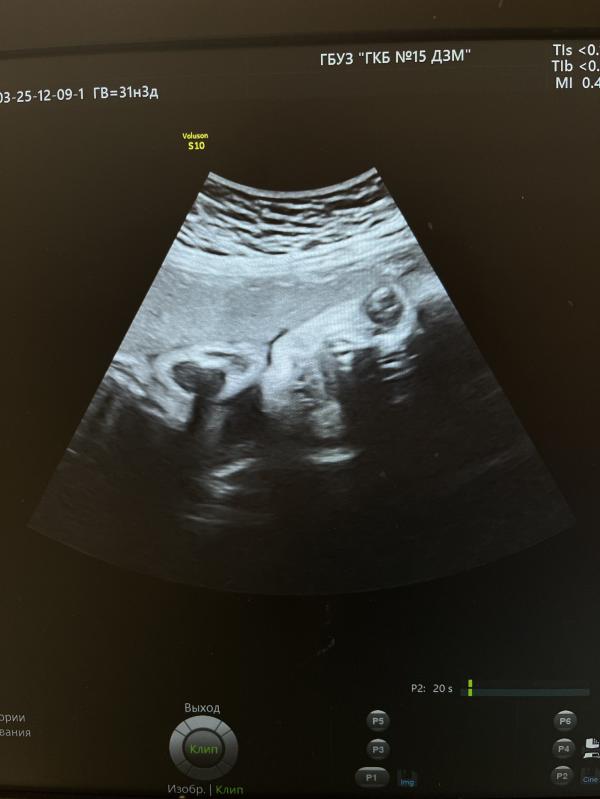

3 скрининг пройден

Вес 1755 +/- 256 гр

ЧСС 150 уд. в минуту

На 9 см выше внутреннего зева

Если еще почитать протокол УЗИ врача, то она пишет «В продольном положении в головном предлежании» и про пуповину «петель достаточное количество»